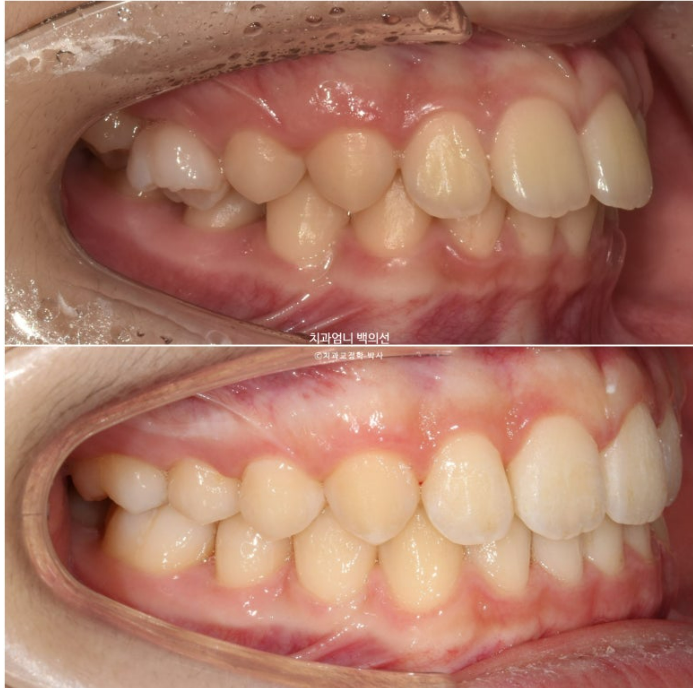

24.03~25.05

첫세트의 장치는 22개가 나왔습니다. 24년 3월부터 24년 9월까지 첫세트의 장치를 모두 낀 후 모습입니다.

24.09

앞니 돌출은 해결이 되었으나 앞니가 깊게 물리는 과개교합이 남아있습니다.